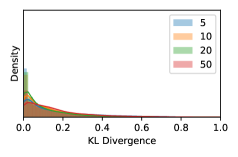

5.1 Distribution of Uncertainty Scores

Distribution of Uncertainty Scores Across Different Severity Levels As explained in Section 3, each uncertainty metric essentially defines an order/ranking among the data points. We conducted an analysis to better understand what data will be assigned high uncertainty under a particular uncertainty metric . Picking out the highest ranked data points (), we calculated the ratio of data points from each SL. Figure 4 summarizes the results as box plots for the Kaggle-DR and the Messidor-2 datasets; additional detailed statistics can be found in Table S.1 in the supplementary materials. From the plot and table, SL1 & SL2 examples account for a higher proportion among the top-ranked uncertain examples across the three ensemble methods. This finding matches our intuition that incipient disease examples (SL1 & SL2) are more likely to be considered uncertain by ensemble methods due to their ambiguity.

Uncertainty Scores on Out-of-Distribution Datasets As an additional experiment, we also tested the performance of the ensemble models on o.o.d. data inputs, which is a classic application of prediction uncertainties [1]. For this task, we produced distribution plots similar to those in Figure 4 for the previous experiment in our supplementary materials. The visualizations for the two o.o.d. image datasets can be found in Figure S.5 for ImageNet and in Figure S.6 for CIFAR-10. The results showed that the majority of o.o.d. data received higher uncertainty scores than in-distribution data for all three ensemble methods, suggesting that these ensemble methods would indeed perform well on o.o.d. detection tasks.

Comparing the three ensemble methods in Figure 4, the stacking ensemble method has the highest ratios of SL1 & SL2 data among the high-uncertainty examples it identified under both mean and var. TTA showed slightly better performance than MC-dropout but still falls behind the stacking ensemble method. Considering the fact that SL0 examples accounted for the majority of the dataset, the stacking ensemble method was much more precise (specific) in selecting truly ambiguous data points that were difficult to classify. From Figure 3, we can also see that the stacking ensemble method greatly outperformed the other two methods in finding false negatives under both mean and var uncertainty metrics.

In contrast, the MC-dropout method showed the worst overall performance among the three, as it can be seen from the high ratios of SL0 examples among the uncertain negatives in Figure 4. The histograms in Figure 2 provides another perspective to look into the phenomenon, where a decent proportion of MC-dropout model’s predictions on SL0 inputs entailed low confidence (far from 0 or 1), which from another angle explained why MC-dropout was less specific in terms of lower FNP; many no-DR inputs (i.e. SL0) were erroneously assigned high uncertainty by MC-dropout models.

As discussed in Section 5.1 and Section 5.3 in the main paper, the mean metric and the stacking ensemble will have better performance in the precision (specificity) on the ambiguous data. Here, more detailed results are shown in Figures S.3 & S.6 and Table S.1. Figures S.3 & S.4 show the histograms of the uncertainty score for Kaggle-DR and Messidor-2 datasets that are the in-distribution (i.d.) dataset in our experiment and FigureS.5 & S.6 show the histograms for ImageNet and CIFAR-10 datasets, which is the o.o.d. datasets in our experiment. Each group of histograms contains results from the three evaluated ensemble methods (stacking ensemble, MC-dropout and TTA) and the three uncertainty metrics (mean, var and kl). Additional detailed results not displayed in Figure 4 can be found in Table S.1, which shows the proportion of the data of different SLs varies across different . For comparison, we also included in Table S.1 the results from single learners, and the proportions of data of different SLs (before any selection was made).